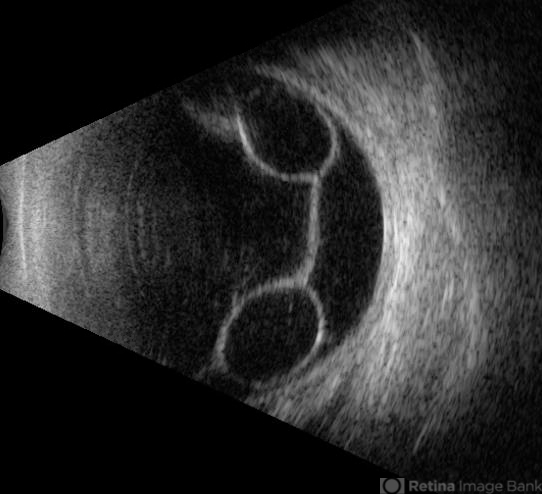

- Ultrasonography of a 55-year-old woman with chronic, symmetric retinal cysts.